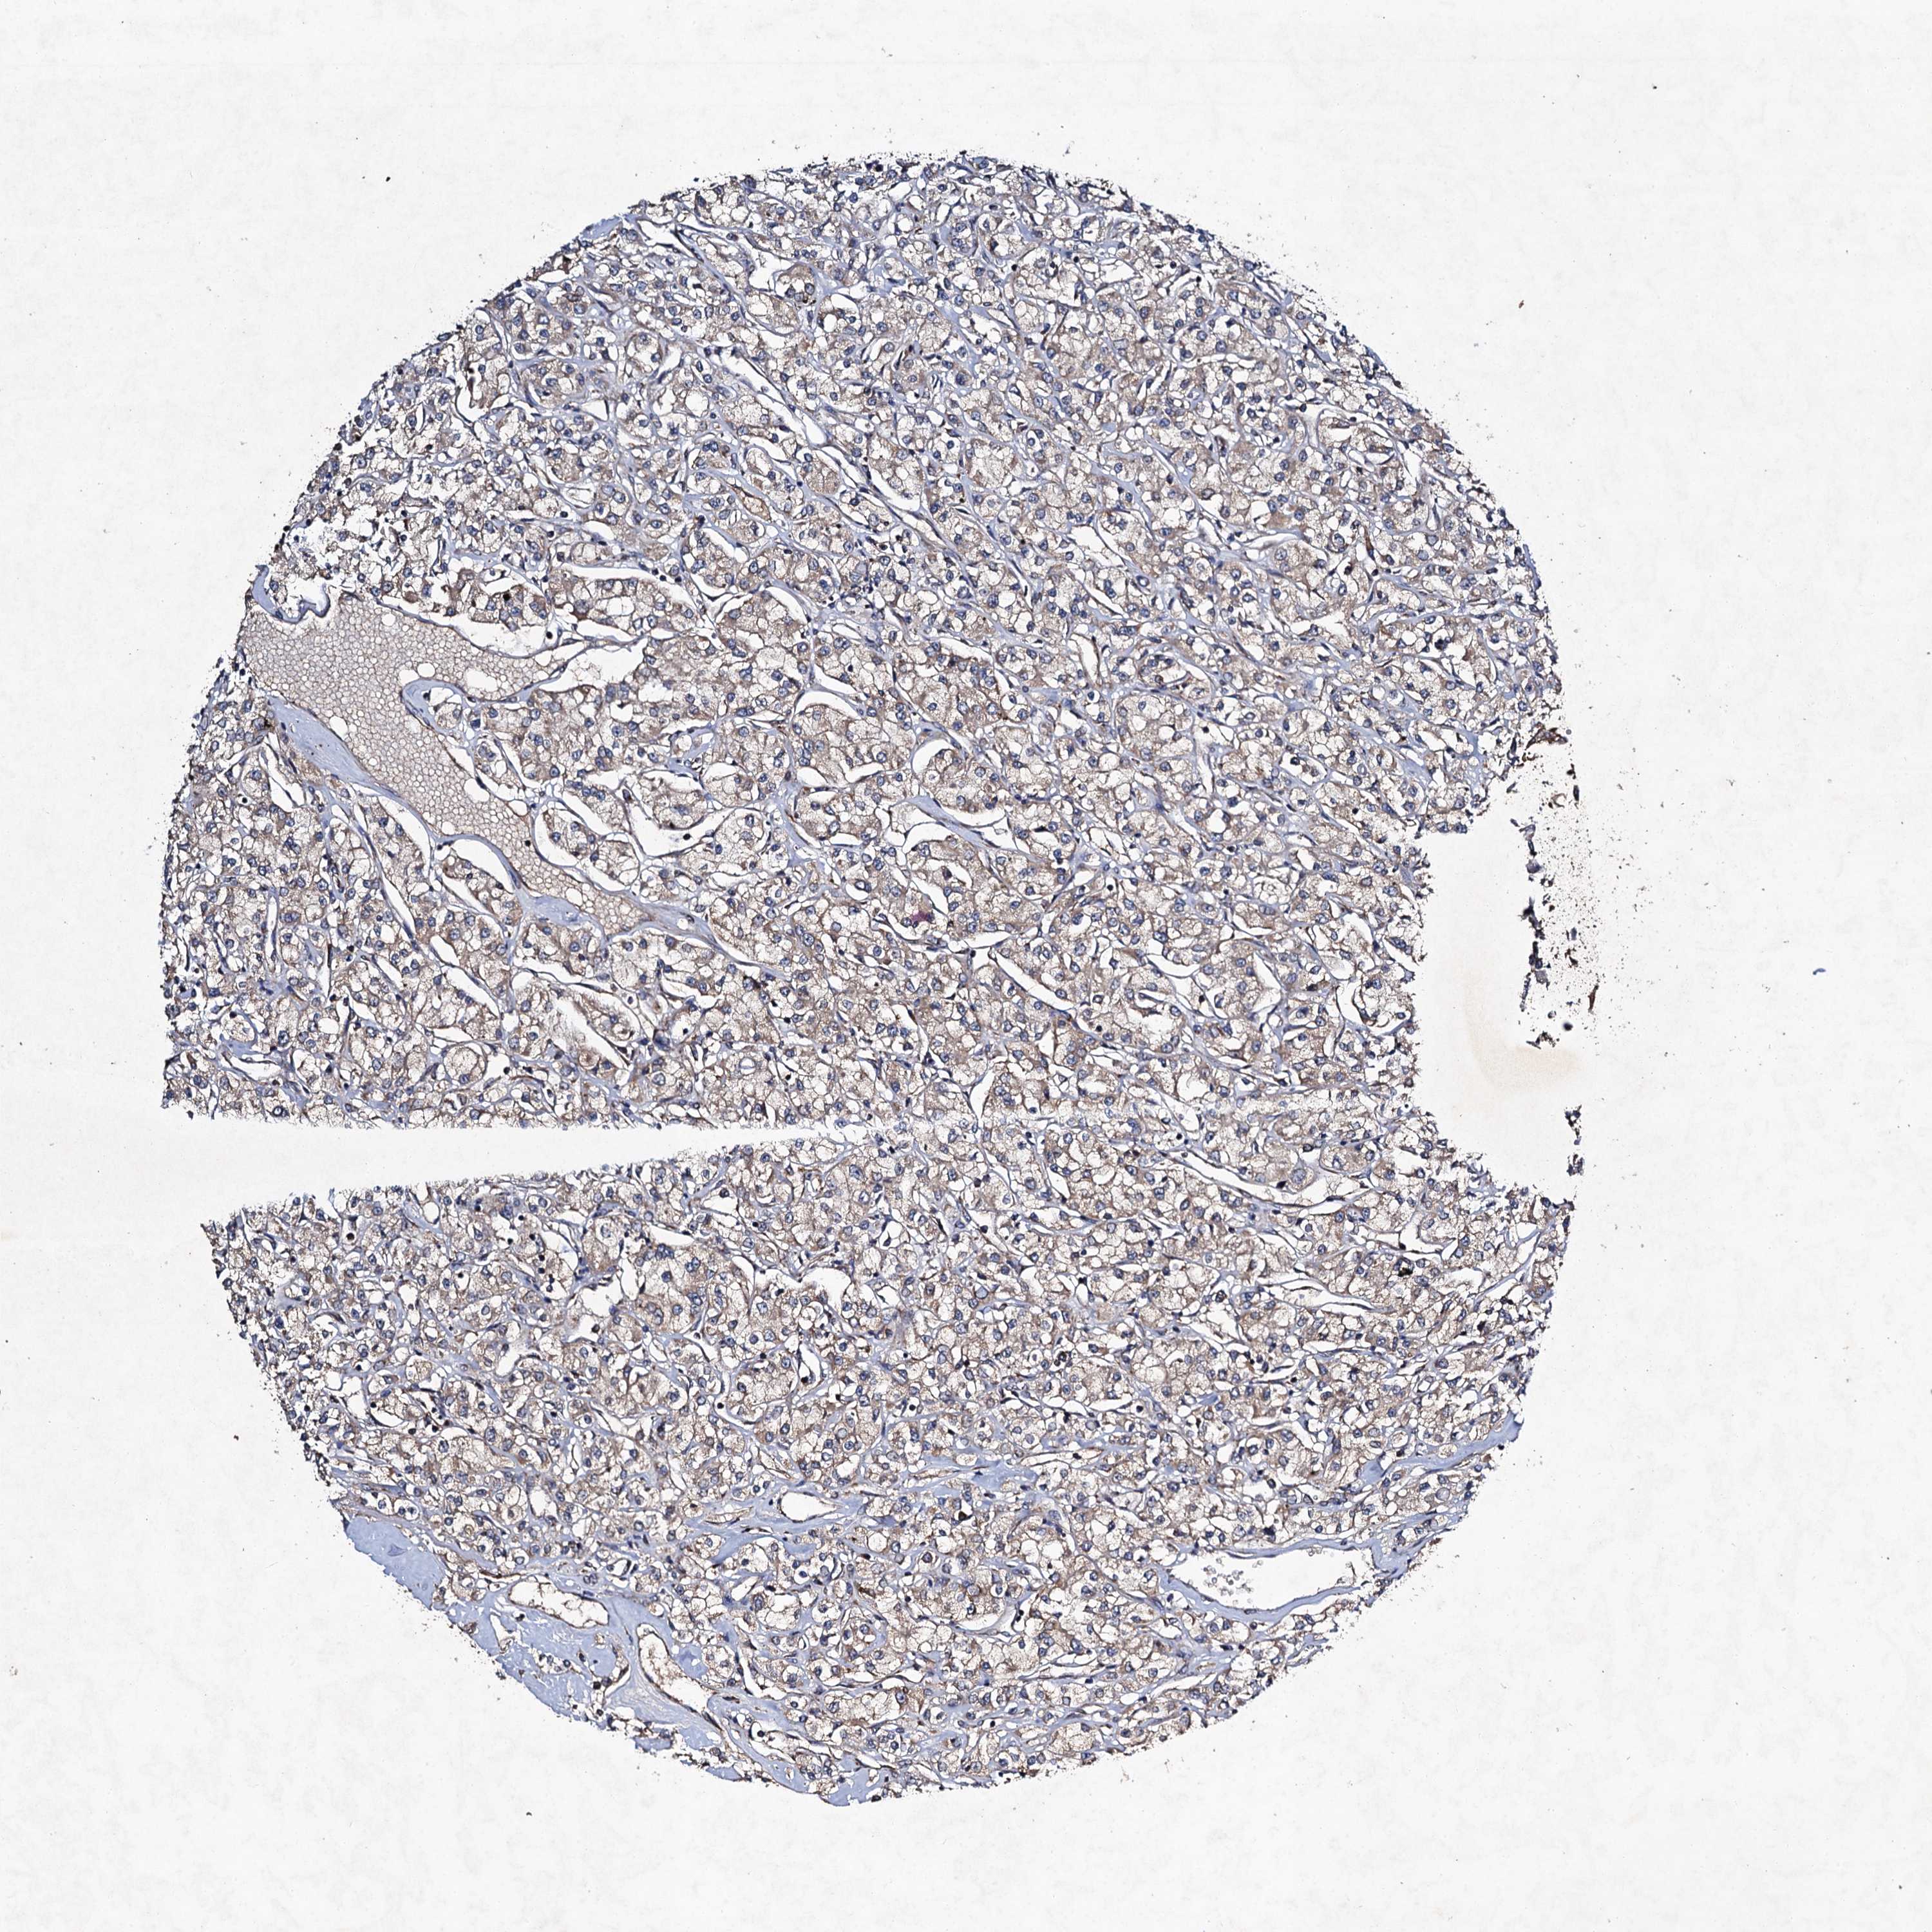

KIDNEY RENAL CLEAR CELL CARCINOMA (VALIDATION) - Interactive survival scatter ploti

The Survival Scatter plot shows the clinical status (i.e. dead or alive) for all individuals in the patient cohort, based on the same data that underlies the corresponding Kaplan-Meier plots. Patients that are alive at last time for follow-up are shown in blue and patients who have died during the study are shown in red.

The x-axis shows the expression levels (FPKM) of the investigated gene in the tumor tissue at the time of diagnosis. The y-axis shows the follow-up time after diagnosis (years). Both axes are complimented with kernel density curves demonstrating the data density over the axes. The top density plot shows the expression levels (FPKM) distribution among dead (red) and alive patients (blue). The right density plot shows the data density of the survived years of dead patients with high and low expression levels respectively, stratified using the cutoff indicated by the vertical dashed line through the Survival Scatter plot. This cutoff is automatically defined based on the FPKM cutoff that minimizes the p-score. The cutoff can be changed by dragging the vertical line or by entering a cutoff value in the square labeled "Current cut-off".

Under the Survival Scatter plot the p-score landscape (black curve; left axis) is shown together with dead median separation (red curve; right axis). Dead median separation is the difference in median mRNA expression between patients who have died with high and low expression, respectively. It is calculated as follows: median FPKM expression of dead patients with high expression - median FPKM expression of dead patients with low expression. This is intended to aid the user in visually exploring custom cutoffs and the associated p-scores and dead median separation.

Individual patient data is displayed and can be filtered by clicking on one or more of the category buttons on the top of the page. Categories describing expression level and patient information include: high, low, alive, dead, female, male and tumor stages. The scale of the x-axis can be toggled between linear and log-scale by clicking on the "x log" button. Mouse-over function shows TCGA ID, patient information and mRNA expression (FPKM) for each patient.

& Survival analysisi

Kaplan-Meier plots summarize results from analysis of correlation between mRNA expression level and patient survival. Patients were divided based on level of expression into one of the two groups "low" (under cut off) or "high" (over cut off). X-axis shows time for survival (years) and y-axis shows the probability of survival, where 1.0 corresponds to 100 percent.

NDUFA13 is not prognostic in Kidney Renal Clear Cell Carcinoma (validation)

Best expression cut offi

Based on the FPKM value of each gene, patients were classified into two groups and association between prognosis (survival) and gene expression (FPKM) was examined. The best expression cut-off refers the FPKM value that yields maximal difference with regard to survival between the two groups at the lowest log-rank P-value. Best expression cut-off was selected based on survival analysis .

When clicking on this number, the vertical dashed line indicating cut-off, the interactive survival plot, and the Kaplan-Meier curve will be adjusted to show results based on the best expression cut-off.

: 459.01

Median expressioni

Median expression refers to the median FPKM value calculated based on the gene expression (FPKM) data from all patients in this dataset. When clicking on this number, the vertical dashed line indicating cut-off, the interactive survival plot, and the Kaplan-Meier curve will be adjusted to show results based on the median expression.

: N/A

Median follow up timei

Median follow up time refers to the median time (years) after diagnosis with this type of cancer, based on clinical data from all patients in this dataset.

P scorei

Log-rank P value for Kaplan-Meier plot showing results from analysis of correlation between mRNA expression level and patient survival.

N/A

5-year survival highi

5-year survival for patients with higher expression than the expression cutoff.

For melanoma and glioma, 3-year survival is shown.

5-year survival lowi

5-year survival for patients with lower expression than the expression cutoff.

TCGA RNA samplesi

RNA-seq data is reported as average FPKM (number Fragments Per Kilobase of exon per Million reads), generated by the The Cancer Genome Atlas (TCGA) .

Normal distribution across the dataset is visualized with box plots, shown as median and 25th and 75th percentiles. Points are displayed as outliers if they are above or below 1.5 times the interquartile range. FPKM values of the individual samples are presented next to the box plot.

Average pTPM 391.2

Number of samples 100